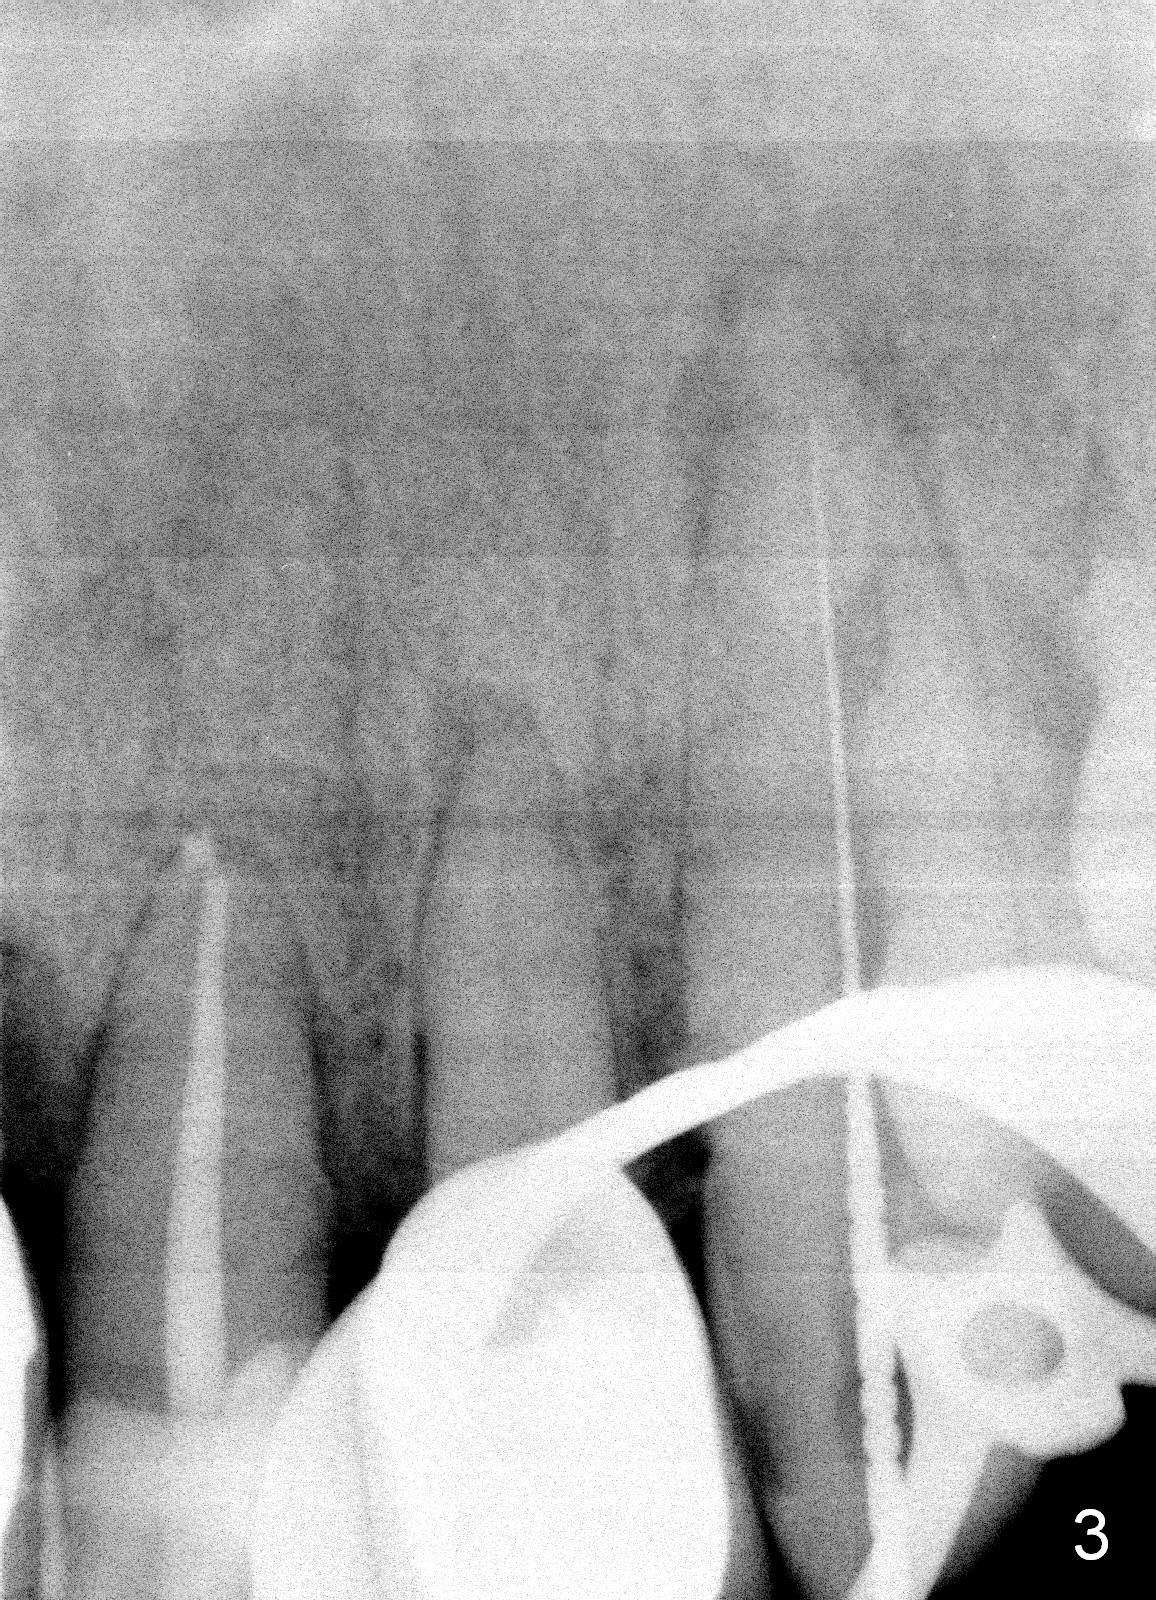

A 57-year-old man has multiple restoration. There was a fistula mesiobuccal to #11 a year ago (Fig.1,2). There is acute apical infection lately. The pulp is non-vital. Apex locator is sensitive. Two PAs are taken with #15 file at 29 mm and 33 mm (Fig.3,4). The canal is debrided until #40 hand file. The master cone with length of 28 mm is inserted below the landmark (Fig.5). Panoramic X-ray is taken for final confirmation (Fig.6).